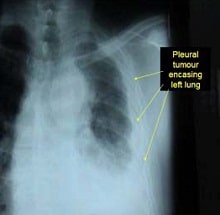

Basically, mesothelioma is a rare type of cancer that affects the outer lining of the organs of the body. This protective covering is called mesothelium.

The major cause of developing mesothelioma cancer is asbestos exposure. Once the asbestos fibers are inhaled or ingested they become lodged in the lung tissues causing chronic inflammation that ultimately result in mesothelioma cancer formation.These cancer cells aggressively spread to different body tissues, eventually making the disease more complicated.